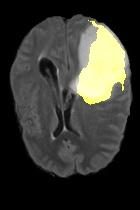

Current unsupervised anomaly localization approaches rely on generative models to learn the distribution of normal images, which is later used to identify potential anomalous regions derived from errors on the reconstructed images. However, a main limitation of nearly all prior literature is the need of employing anomalous images to set a class-specific threshold to locate the anomalies. This limits their usability in realistic scenarios, where only normal data is typically accessible. Despite this major drawback, only a handful of works have addressed this limitation, by integrating supervision on attention maps during training. In this work, we propose a novel formulation that does not require accessing images with abnormalities to define the threshold. Furthermore, and in contrast to very recent work, the proposed constraint is formulated in a more principled manner, leveraging well-known knowledge in constrained optimization. In particular, the equality constraint on the attention maps in prior work is replaced by an inequality constraint, which allows more flexibility. In addition, to address the limitations of penalty-based functions we employ an extension of the popular log-barrier methods to handle the constraint. Comprehensive experiments on the popular BRATS'19 dataset demonstrate that the proposed approach substantially outperforms relevant literature, establishing new state-of-the-art results for unsupervised lesion segmentation.